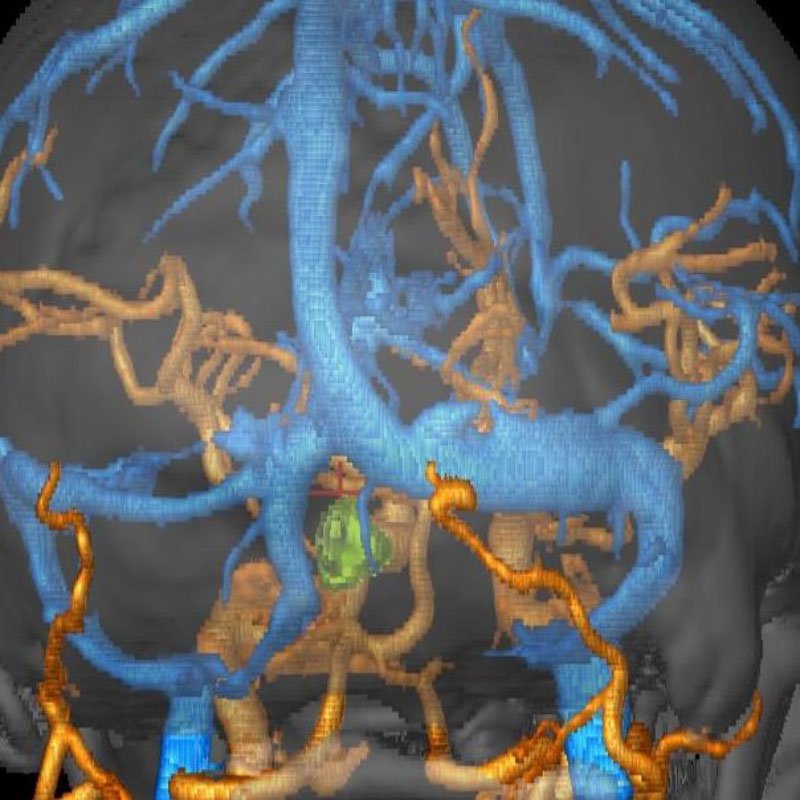

'19年11月

40代

富永

南田

基底核

海綿状血管腫

出血性

兵庫県の病院

より紹介

CT/MRにより完全に摘出されたことが確認された